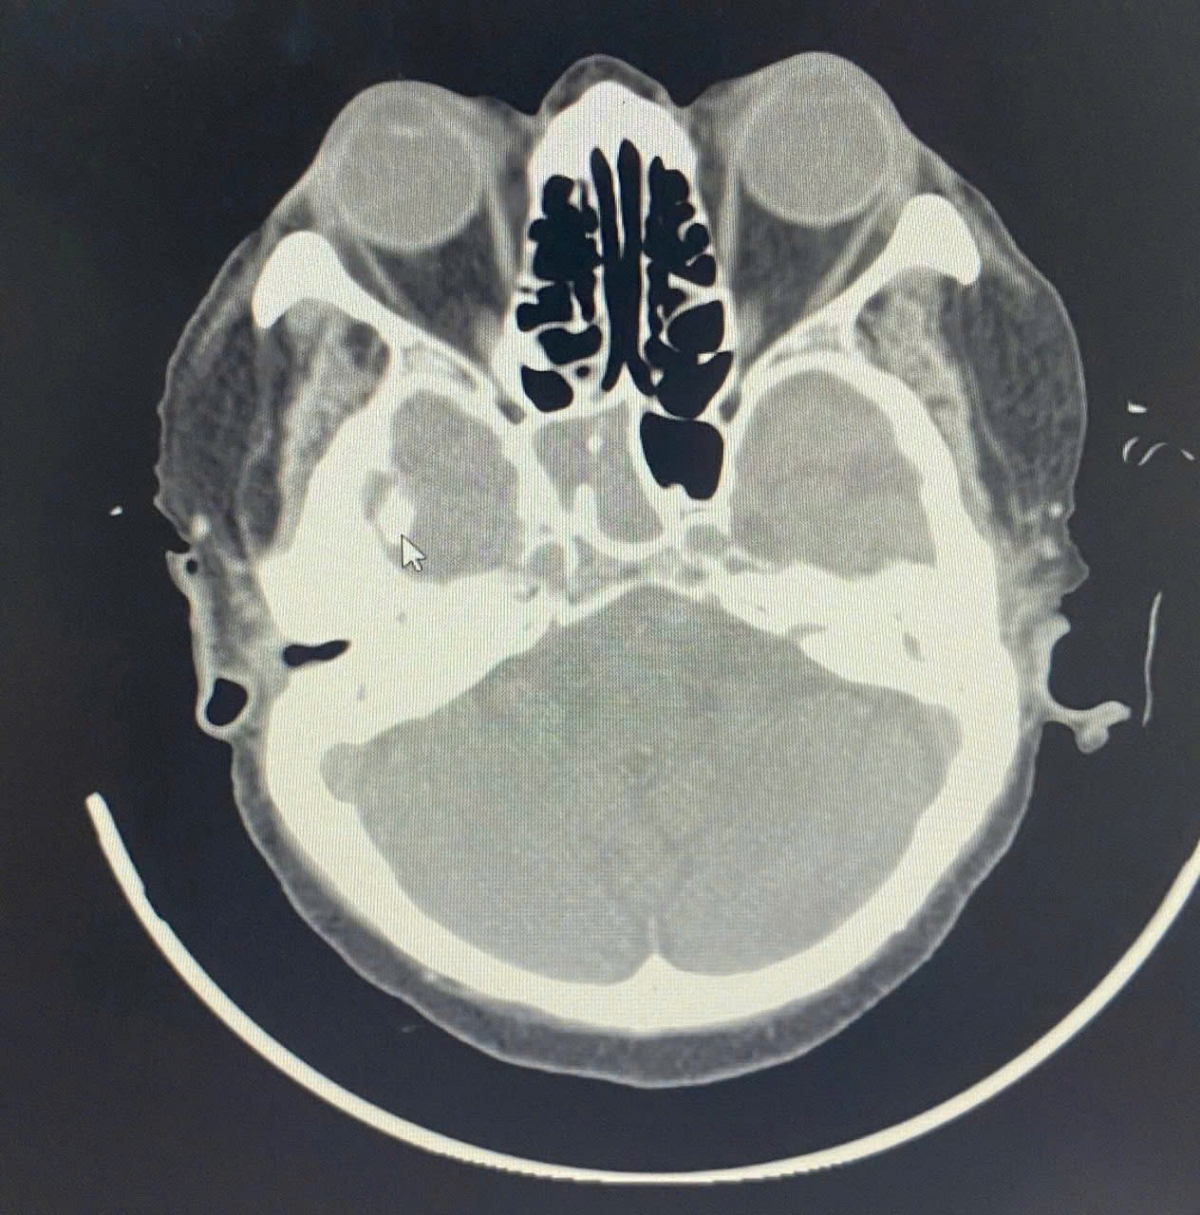

Hình ảnh chụp cắt lớp vi tính viêm xoang bướm bên phải

Bệnh nhân nữ, nhập viện trong tình trạng đau đầu dữ dội kéo dài suốt nhiều tuần, kèm mệt mỏi và mất ngủ, đau nhức vùng đỉnh chẩm, sau gáy, đau sâu 2 hốc mắt. Kết quả chụp cắt lớp vi tính (CT) cho thấy xoang bướm phải bị mờ đặc, tổn thương nghĩ đến nấm xoang. Đây là vị trí nằm sâu trong nền sọ, gần thần kinh thị giác và động mạch cảnh trong – nơi chỉ cần một ổ viêm lan rộng cũng có thể gây mù mắt, viêm màng não hoặc nhiễm khuẩn huyết.